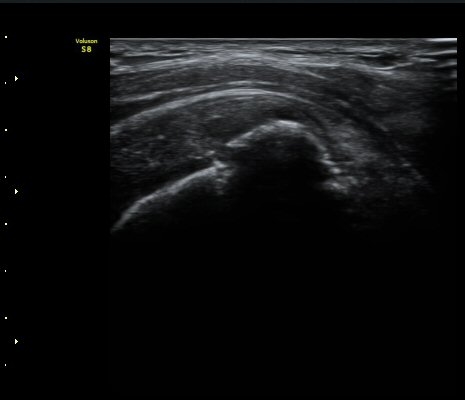

¼ºº° / ³ªÀÌ

¿©ÀÚ/ 50¼¼

ÁÖÁõ»ó

³Ñ¾îÁø ÈÄ ½ÉÇØÁö´Â ¾î±úÀÇ ÅëÁõ°ú °­Á÷

º´·Â

³Ñ¾îÁø ÈÄ ¾î±úÀÇ ÅëÁõÀÌ ¹ß»ýÇÏ¿© Ÿ º´¿ø ³»¿øÇÏ¿© ¿¢½º·¹ÀÌ °Ë»ç¿¡¼­ ƯÀÌ ¼Ò°ß ¾ø´Ù´Â ¼Ò°ßÀ» µè°í Áö³ÁÀ¸³ª ¾î±úÀÇ ÅëÁõÀÌ ½ÉÇØÁö°í Á¡Á¡ ¾î±ú°¡ ±»¾îÁ® ³»¿ø

ÃÊÀ½ÆÄ °Ë»ç